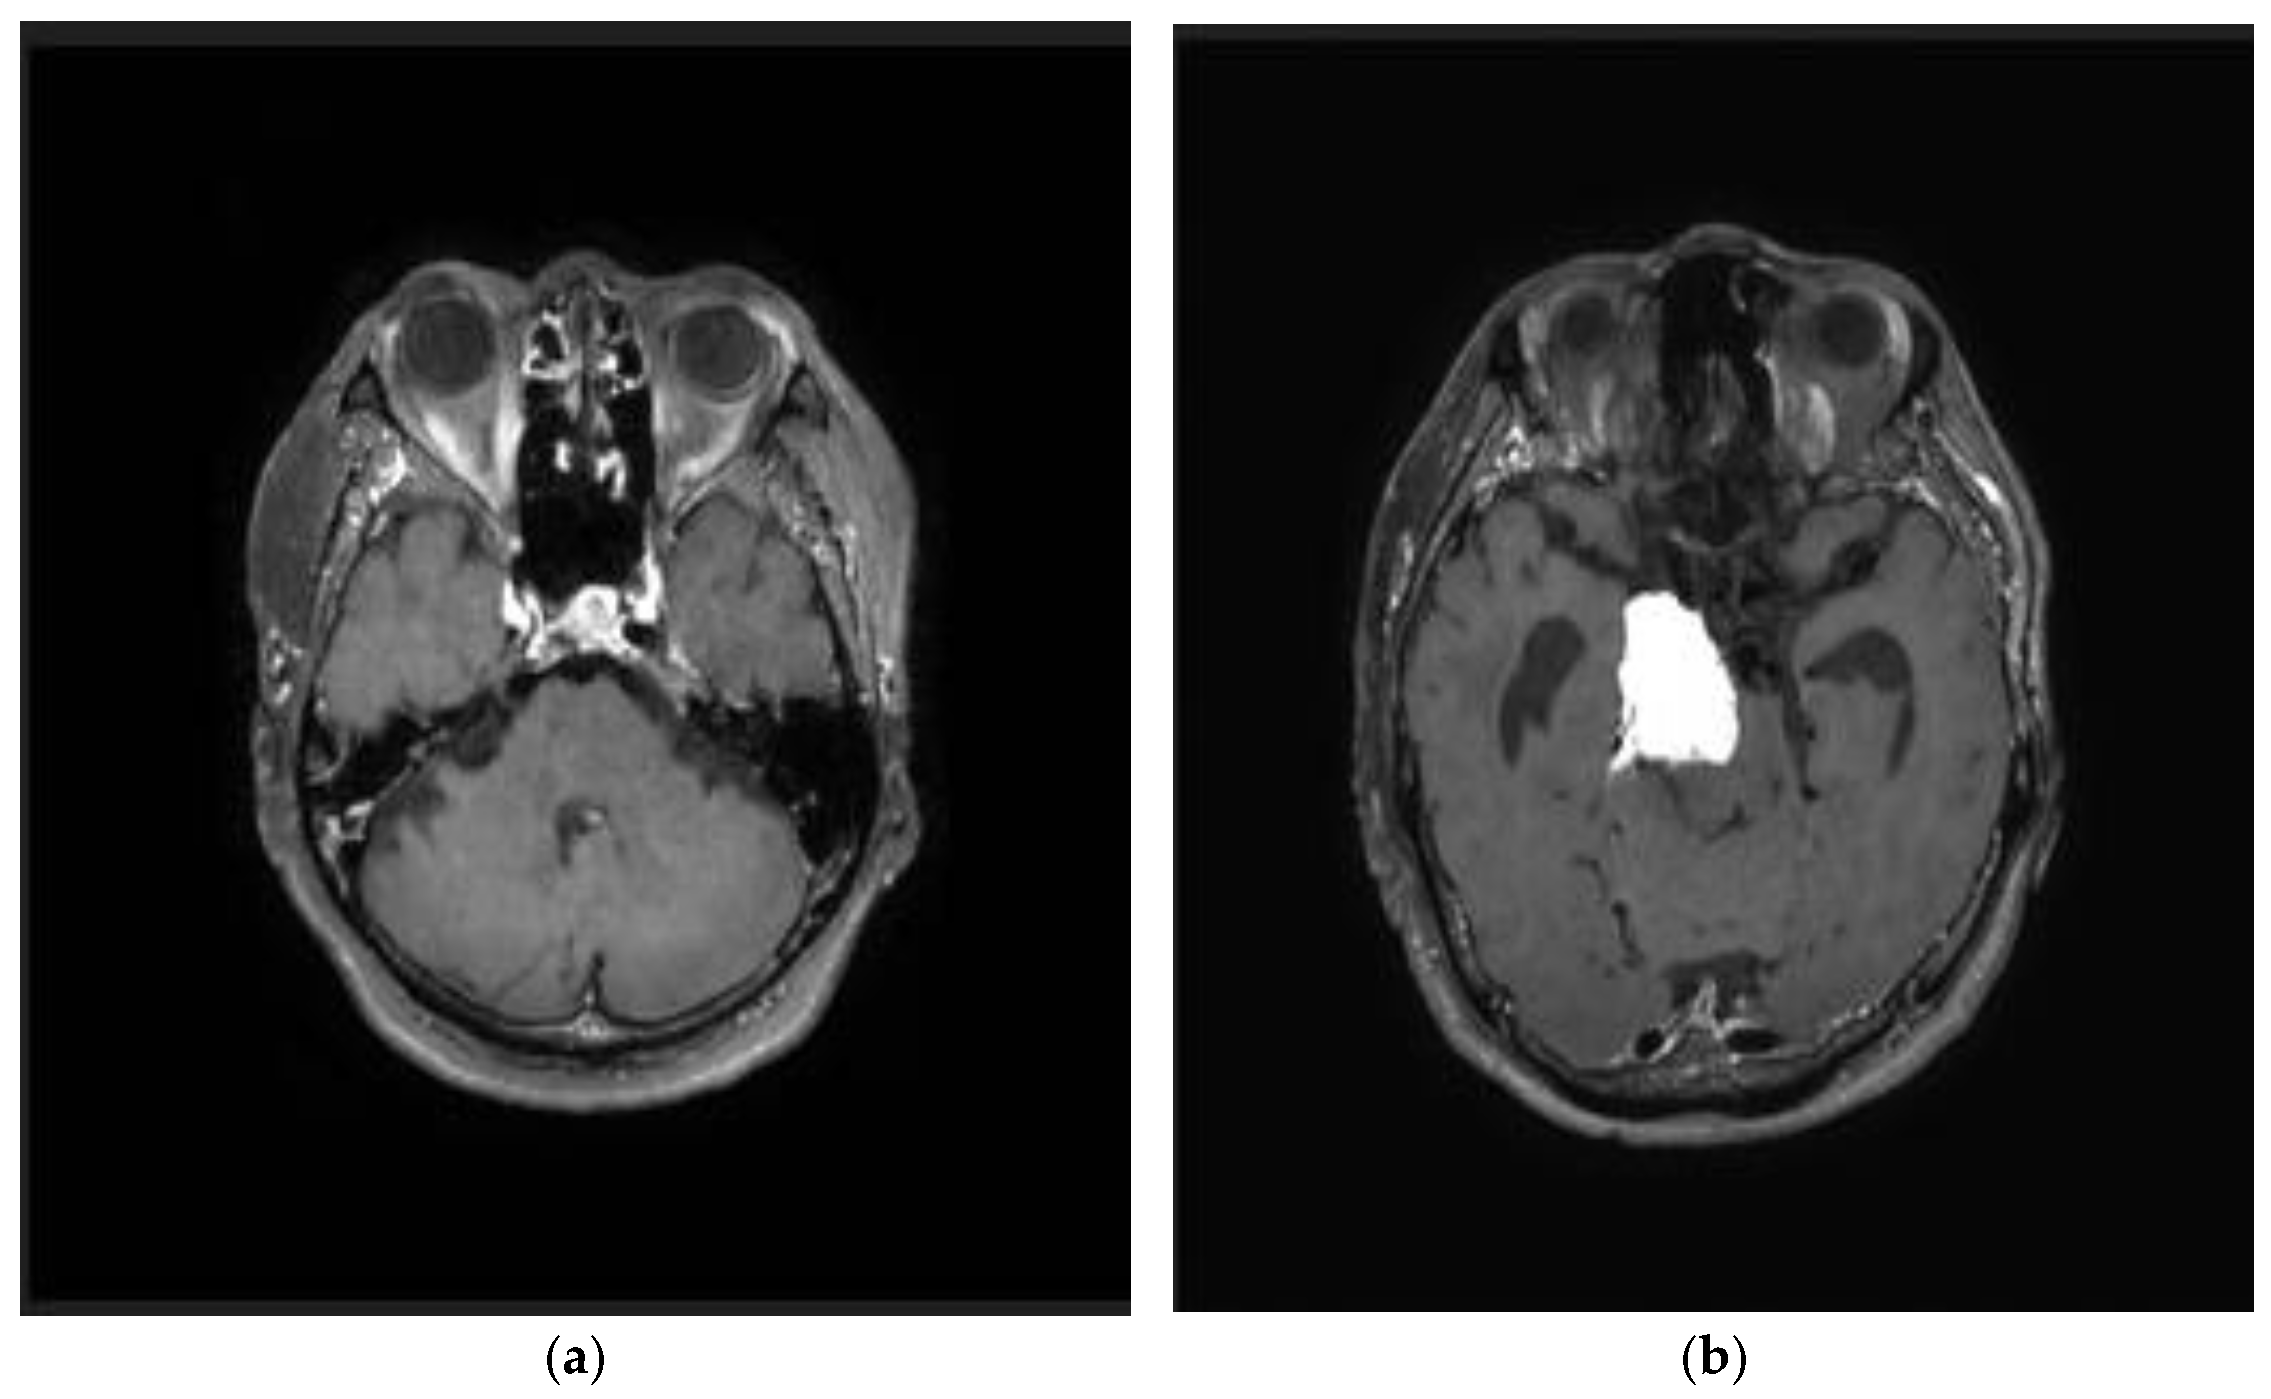

3.1. Dataset